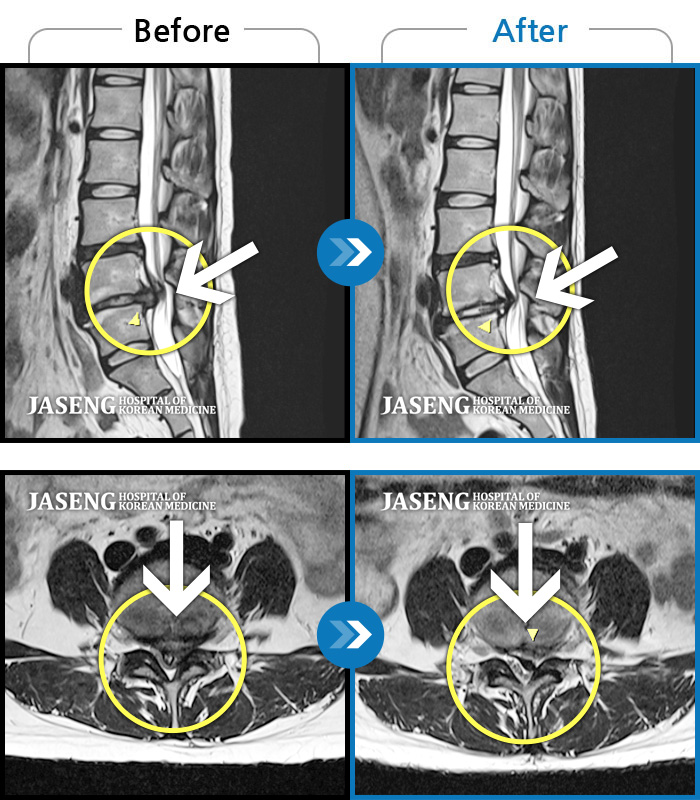

Before

After

환자에게 사전 동의를 받아 동일 조건에서 촬영되었습니다.

개인에 따라 치료 후 부작용이 발생할 수 있으니 의료진과 상담 후 치료를 진행하시기 바랍니다.

양쪽 허리, 엉치, 골반쪽으로 불편감, 우측 다리 저림

허리 우측 골반에서 발목으로 통증